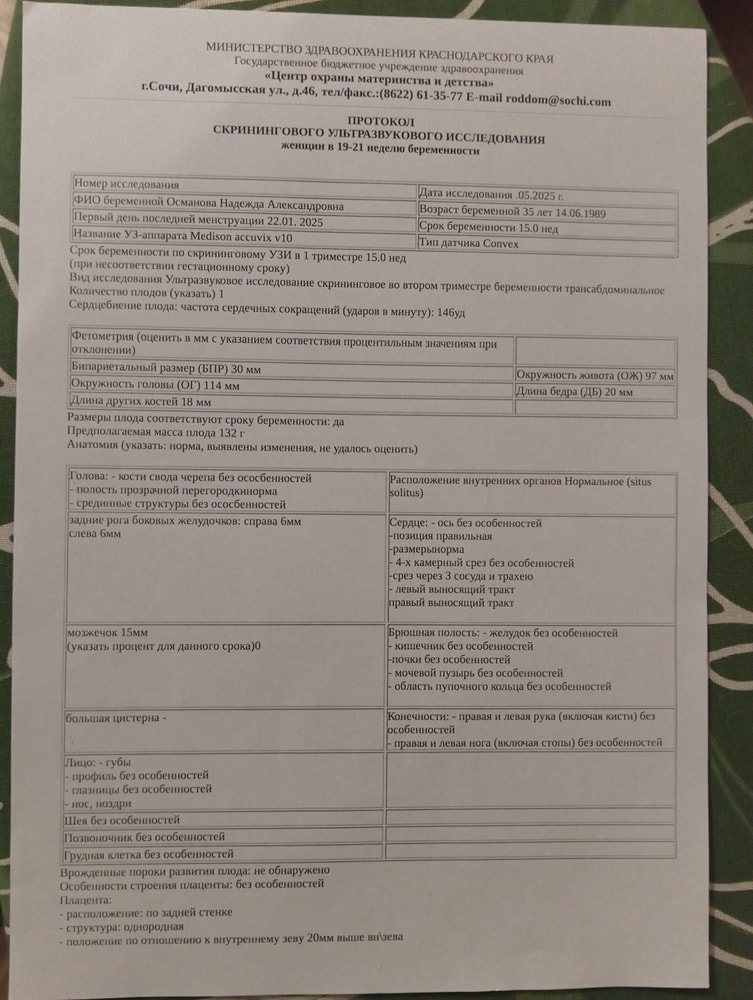

Как может быть 132 гр когда по всём таблицам 50-70 гр. Рост не указан. Сказали всё в норме, соответствует норме. Но мне не понятно.

Странное УЗИ, вес плода 15 нед и 0 дней

Вбейте свои показатели в калькулятор расчета веса. Если покажет тоже самое, значит ошибка либо в измерениях, либо в сроке. На 3 недели не видела чтобы спешили дети, мой на 2 спешит, но недели с 20 только

Элементарно может быть. Может чуть с опережением развивается (особенно отдельные части) + вам наверняка доверительный интервал поставили (133+/- сколько-то там)